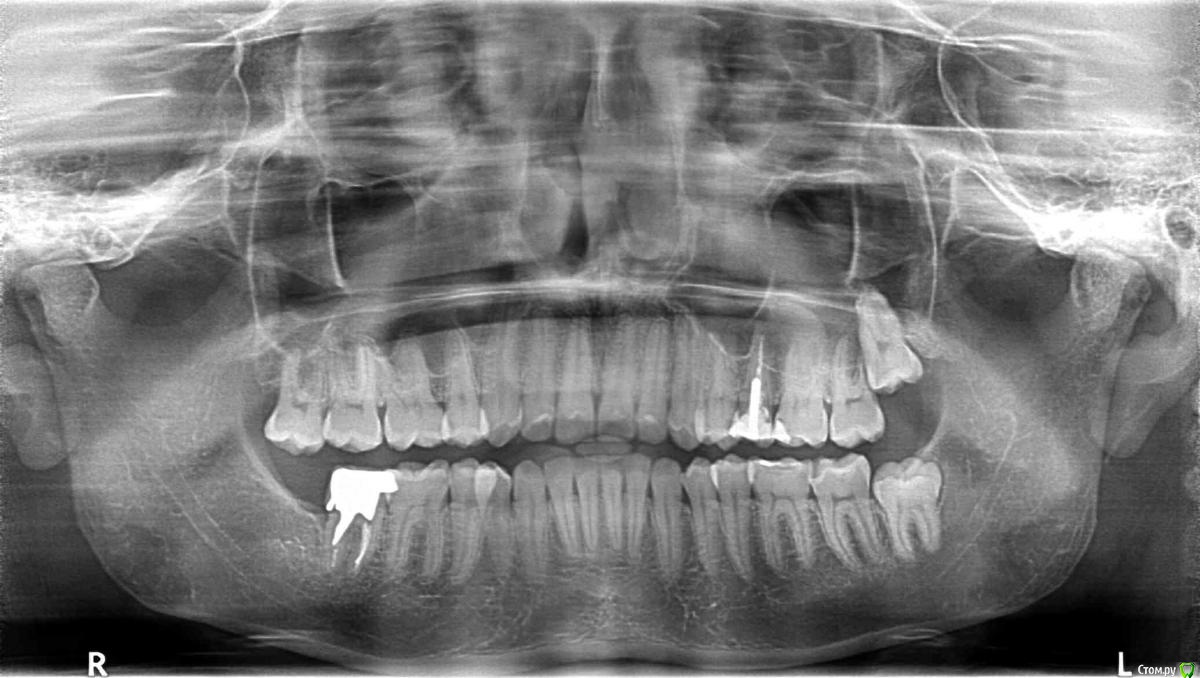

Katerina) Опубликовано 22 августа, 2015 Поделиться Опубликовано 22 августа, 2015 Добрый вечер! Прошу помочь разобраться. Около года назад на нижний зуб поставили коронку, на культиевую вкладку, с тех пор болит десна с одной стороны. Боль не сильная, только при надавливании на десну или часть зуба. На прошлой неделе сняли коронку, боли в первые 3 дня не было, а сейчас когда я полноценно ем на этой стороне, боль снова появилось. Что это может быть? Для наглядности прикладываю снимок. Ссылка на комментарий

voff Опубликовано 24 августа, 2015 Поделиться Опубликовано 24 августа, 2015 (изменено) В процесс вовлечен пародонт (кость вокруг зуба, связочный аппарат десна) и уже образовался костный карман. Если кто-то из пародонтологов-хирургов возьмется лечить такой зуб, то хорошо. Но на мой взгляд- это бомба замедленного действия и исход один- удаление Изменено 24 августа, 2015 пользователем voff Ссылка на комментарий

shishok Опубликовано 24 августа, 2015 Поделиться Опубликовано 24 августа, 2015 Я бы для начала удалила 18 зуб(восьмой вверху справа).У него нет антагониста и он сместился вниз,может травмировать десну на нижней челюсти.ИМХО. Ссылка на комментарий